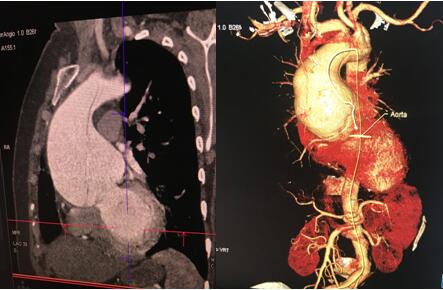

术前CTA影像:升主动脉扩张明显,最大直径10cm

术前升主动脉瘤样扩张和术后人工血管置换后